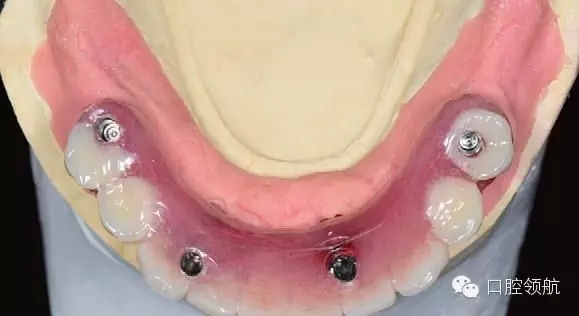

手術當天取模,當天灌注石膏模型,上牙合架,開始準備制作螺絲固定的過渡義齒(圖6-11,圖6-12)。

圖6-11 安放閉口轉移桿后的牙合面照

圖6-11可見前牙區(qū)轉移桿與后部轉移桿之間有十幾度的角度偏差,前牙區(qū)沒有使用角度復合基臺來調整角度。雖然可以使用17°的角度復合基臺調整螺絲開孔角度,使前部及后部的就位道更接近平行,但是因為這樣就加大了前牙區(qū)的義齒厚度,容易造成舌體的不適,因此下前牙區(qū)在使用角度復合基臺調整過于唇傾的種植體方向時,需要慎重并事先與患者溝通。